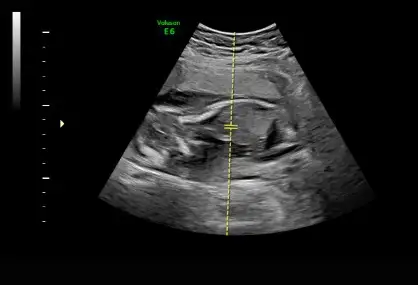

Kız demişlerdi sana değil mi canımÇıkıntıdan geçmiş kocamandiherif hala guluyo gevrek gevrek

Öyleymiş cnm hayallerimi yiktiErkek mi

Baya kiz yaa yüzde 100 demişti smdide yok erkek dedi değişmez dediKız demişlerdi sana değil mi canımerken haftalarda belli olmayabiliyor karıştırıyor bazen doktorlar hayırlı olsun oğluşun

Kendi bebeğimin cinsiyeti değişmiş gibi şaşırdım vallaBaya kiz yaa yüzde 100 demişti smdide yok erkek dedi değişmez dedi

Çok fena soklardayim inanmadım zaten dalga geciyo sandım hadi ordan falan dedm bak bak diye odaklayincaKendi bebeğimin cinsiyeti değişmiş gibi şaşırdım vallabaya şok olmuştur sana Allah sağlıkla kucağına almayı nasip etsin oğluşunu

Boşuna demiyorum detaylı ultrasonda doktor onaylamadıkca cinsiyete kesin gözüyle bakmam diyeÇok fena soklardayim inanmadım zaten dalga geciyo sandım hadi ordan falan dedm bak bak diye odaklayincaÇok şükür Sağlıklı o önemli olan tabii de hala şoktan çıkamadım yalan yok

Salı günü benim de kontrol var bakalım en son kız demişti ben de ya pipi görürsem diye düşünmeye başladımÇok fena soklardayim inanmadım zaten dalga geciyo sandım hadi ordan falan dedm bak bak diye odaklayincaÇok şükür Sağlıklı o önemli olan tabii de hala şoktan çıkamadım yalan yok

Ben sana hep dedim nedense inanmıyorum bu bebek erkekKızlaaar ben geldim bgun kontrol vardi çok şükür saglikliymisbide sürpriz getirdim

Ben sana hep dedim nedense inanmıyorum bu bebek erkek

Boşuna demiyorum detaylı ultrasonda doktor onaylamadıkca cinsiyete kesin gözüyle bakmam diyegüven olmaz bu bebelere çok değişen duydum gördüm

Salı günü benim de kontrol var bakalım en son kız demişti ben de ya pipi görürsem diye düşünmeye başladımkızım demeye çok alıştım valla tabi önce sağlıklı olması önemli ama doktor yanıldıysa ben de şoka girerim

Ysmnondr valla ben de çok şaşırdım senin kızın olacağına baya iknaydım ben sen artık iyice şok olmuşsunsun Rabbim sağlıcakla kavuştursun

Sağlıklı olsun gerisi hiç önemli deil tabii çok şükür kıpır kıpırdı bebisim o bile bana yetti ama yalan yok o an çok fena bozuldum allah affetsinBana da teyzem ben 6 aylıkken kız olduğunu öğrendim o zamana kadar hep erkek dediler dedi beni şüpheye düşürdü ben artık emin olamıyorum

Ama kötü oluyo yaa alışıyosun kabulleniypsun benimsiyosun sonra pat yok bu erkek